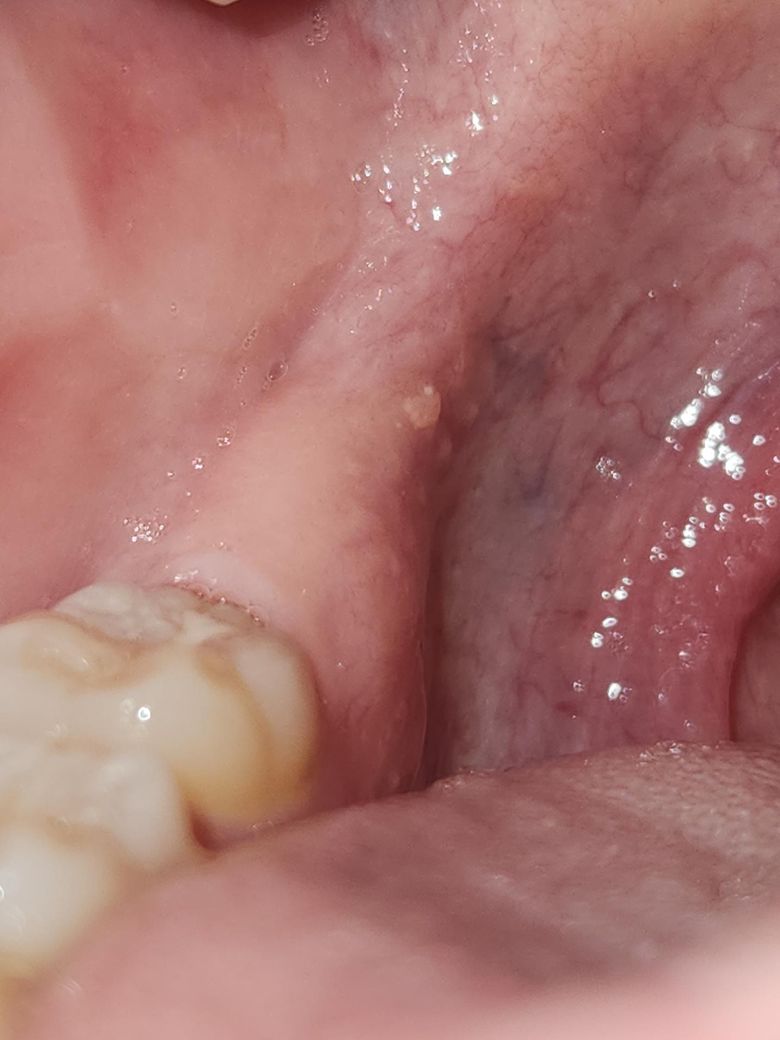

어금니 뒤쪽 입안에 난 하얀게 뭘까요?

아프지는 않고, 5일 전 발견했습니다.

약간 튀어나와 있는데 심각한 건 아니겠죠?

단순 지방종(lipoma)이거나 특정한 음식물에 의해서 자극되어 잇몸이 부풀어 올랐을 가능성이 있습니다. 다만 정확한 판단을 위해서는 조직검사를 시행해보아야 합니다. 모양이나 해당 부위로 판단했을 때는 큰 문제가 되지 않으나 너무 걱정이 된다면 대학병원 방문 후 해당 부분을 조직검사(biopsy)로 확인해보는 것이 좋을 수도 있습니다.

사진이 흐려 명확하지는 않으나 구강내에서 생길 수 있는 일종의 사마귀양의 양성종양 또는 유두종 등으로 보입니다. 크기가 지속적으로 커질 수 있으며 정확한 것은 제거 후 조직검사해봐야 알 수 있습니다.

크기가 작으므로 경과관찰도 가능하나 되도록이면 구강악안면외과 내원하셔서 검진 받아보시기를 권유드립니다